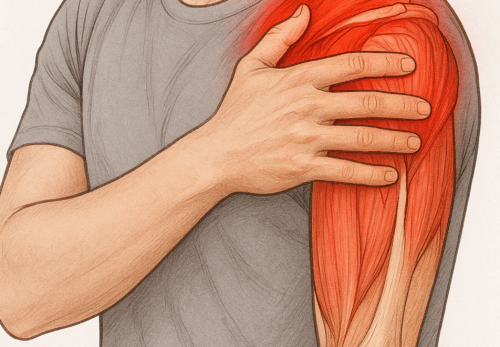

・投球動作で酷使される前腕屈筋群・伸筋群の過緊張を緩和

・肘関節だけでなく、肩・肩甲骨・体幹の連動性を高めるための施術

・血流改善による回復促進

単に痛みを抑えるだけでなく、投球フォームや身体全体のバランス改善を見据えたケアが重要です。比較的早期の受診であれば保存療法が中心ですので、その間、鍼灸で治療することにより回復を早めサポートしていくことが可能です